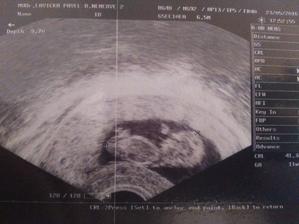

15.5. první KO u dr. potvrzeno těhotenství 6tt (gestační a žloutkový váček)

29.4. druhá KO u dr 7+3, 12,3mm a srdíčko bije

23.5. pro průkazku + odběr krve + utz 11+0 mimisek 4,2cm